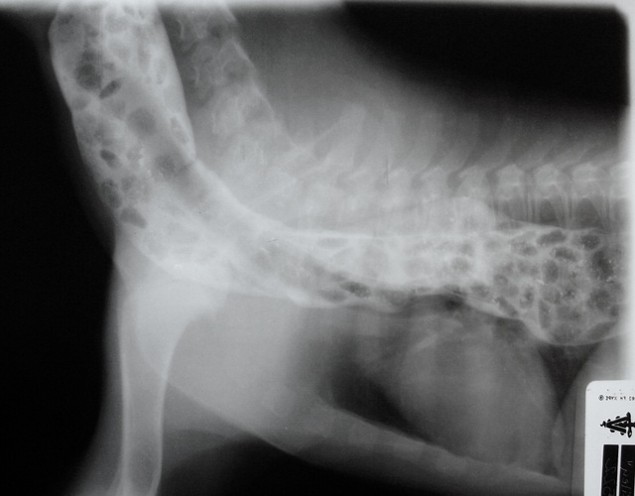

1

Radiography - Puppy